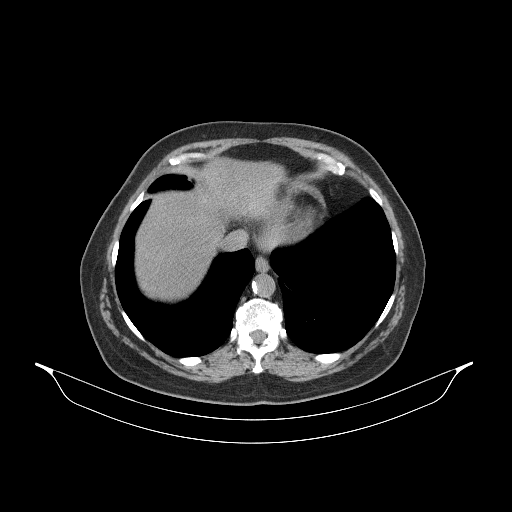

Image Grid

4Γ—3 grid: Rows show different image types (Original NATIVE, Reconstructed NATIVE, Original VENOUS, Generated VENOUS), Columns show windowing techniques (No Window, Lung Window, Mediastinum Window)

Reconstructed NATIVE CT scan (cycle consistency)

Mediastinum window (WL 40, WW 400 β†’ Low βˆ’160, High +240)